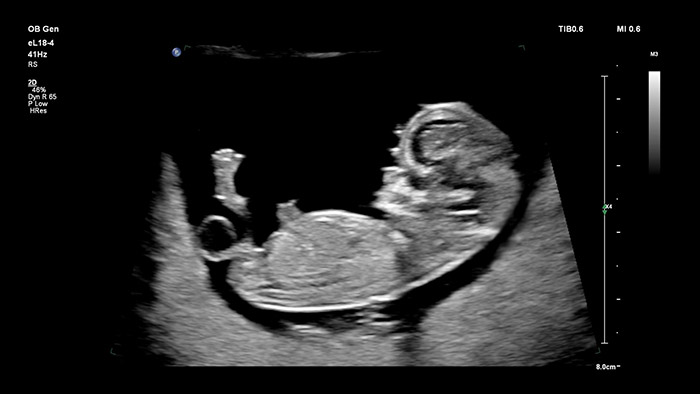

O transdutor eL18-4 da Philips com MicroFlow Imaging derruba barreiras com imagens 2D de alta resolução e detecção de fluxos sanguíneos ultrassensíveis para avaliar a saúde geral do feto nas primeiras fases da gravidez, nas quais é essencial ter uma excelente resolução e confiança no diagnóstico. Extremamente versátil e exclusivamente concebido para exames obstétricos, o transdutor V9-2 utiliza o poder da tecnologia de cristais PureWave para fornecer excelentes imagens 2D e 3D, ao mesmo tempo que permanece leve para a sua classe.